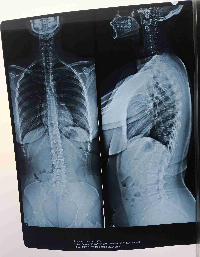

Me chamo Tâmara, mais conhecida como Tammy.Sou protetora independente da causa animal e recentemente descobri que estou com problema gravíssimos na minha coluna, o que me impede de continuar ajudando na causa, mas os animais que eu já cuido, dependem de mim. Preciso fazer meu tratamento com urgência, e tenho também que ter um veículo para manter o meu deslocamento porque a moto que eu usava era emprestada e a dona pegou de volta.Vou deixar as imagens dos meus exames abaixo para que vocês possam entender o que está acontecendo, mas já adianto que eu estou com vários problemas, como ESCOLIOSE, LESÃO NA LBAR, DESIDRATAÇÃO DISCAL, Protrusão discal entre outros.Infelizmente tudo isso tem me impossibilitado de manter as minhas atividades diárias, inclusive a de carregar pacotes de ração, garrafas de água e remédios para distribuir diariamente.